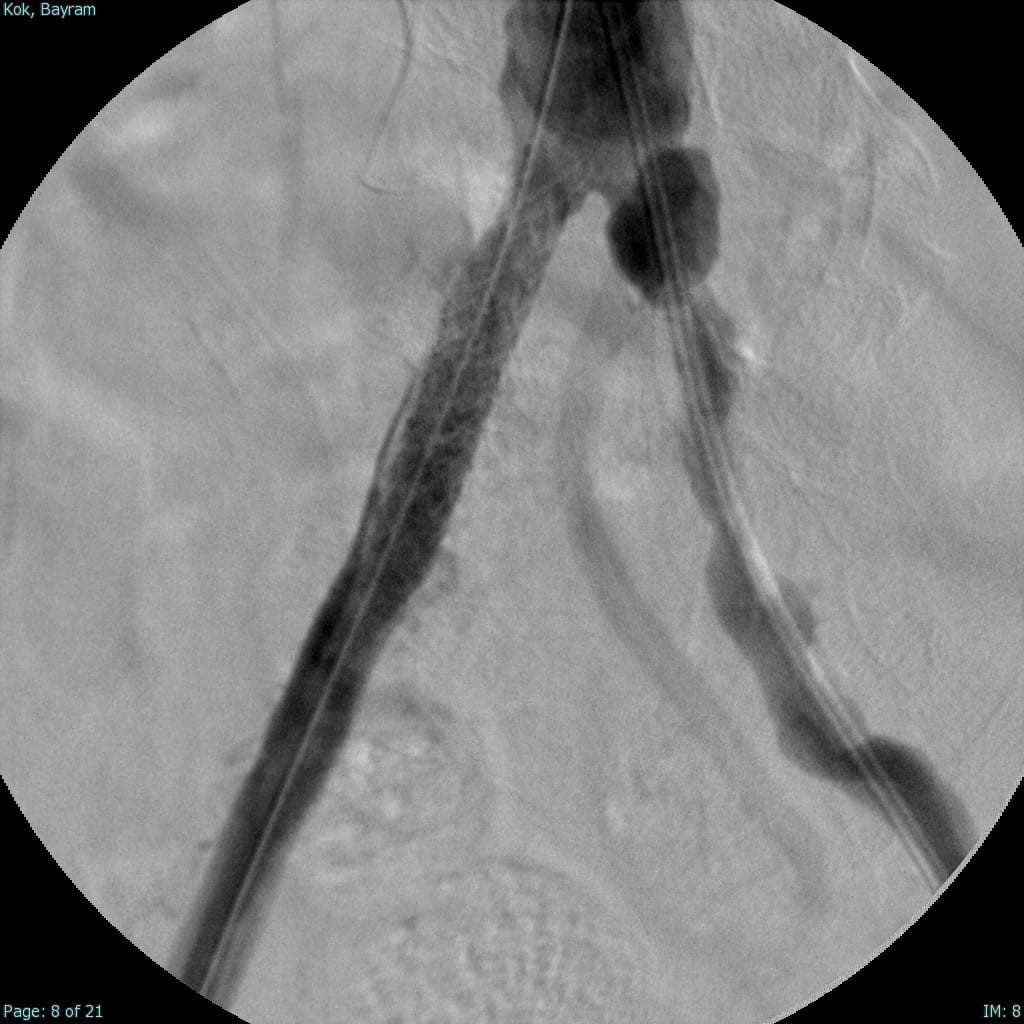

Türkiye’nin ilk yerli stent grefti Bezmiâlem Vakıf Üniversitesi Tıp Fakültesi’nde Prof. Dr. Cengiz Köksal ve Doç. Dr. Emre Selçuk’un öncülüğünde Artven koordinasyonuyla bir hastaya başarıyla uygulandı. Doç. Dr. Emre Selçuk, bu büyük adımı şöyle değerlendirdi:

"Stent-greft teknolojisi, damar tedavilerinde kritik bir rol oynuyor. Damar balonlaşması veya yaralanma riski olan hastalarda bu teknolojinin önemi daha da artıyor. Artık bu teknolojiyi Türkiye’de üretiyor olmamız, operasyon başarımızı artırmanın yanı sıra, hasta güvenliğini de üst seviyelere taşıyacaktır. Türkiye’nin tıbbi alandaki bu başarısında yer almaktan büyük gurur duyuyoruz. Atlas Stent Greft, Türk mühendisliğinin ve Türk doktorlarının inovasyonunun ne kadar ileri seviyede olduğunun bir göstergesidir."